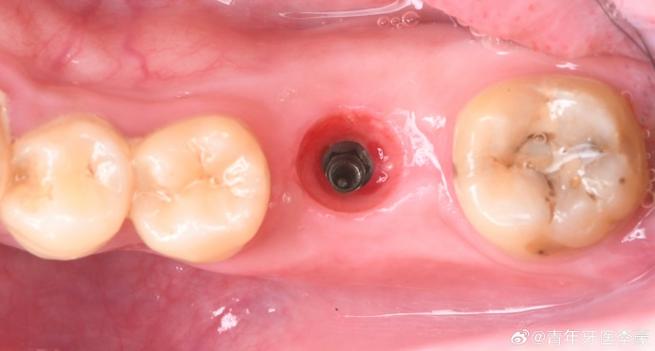

种植体植入位置或角度偏差:

(图片来源网络,侵删)- 位置不佳: 种植体植入时没有完全处于理想位置(如偏向唇颊侧或舌腭侧),导致最终牙冠无法与邻牙紧密贴合,形成缝隙。